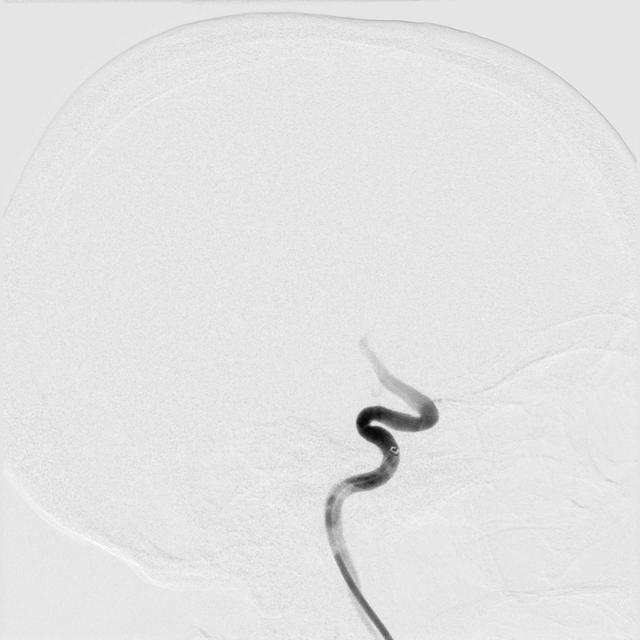

Within my PhD project, we are developing computer vision methods to automatically analyze cerebral Digital Subtraction Angiography (DSA) images. This includes automatic detection of vessel occlusions, quantifying vessel differences between the pre- and post-treatment DSA or delineating brain regions on DSA. The ultimate goal of these methods is to support clinical decision-making during mechanical thrombectomy procedures.